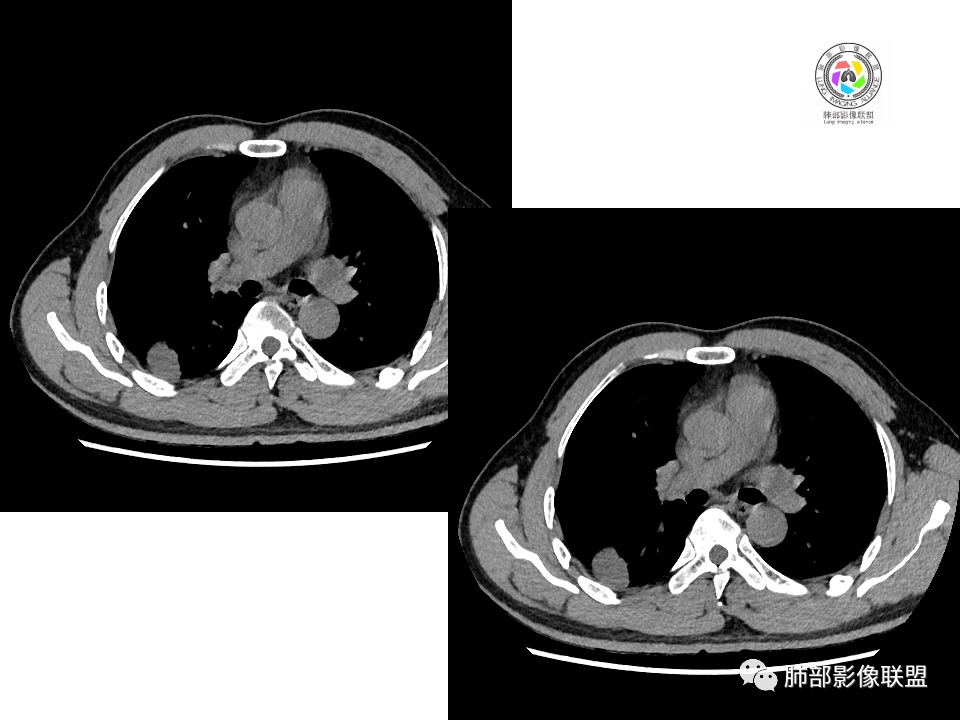

男性,49岁,体检发现,右肺下叶背段胸膜下见肿块,边界清楚,边缘光滑,胸膜下脂肪间隙存在,有分叶,无毛刺,均匀强化,内无坏死,右肺下叶血管束间不规则实性结节,边界清楚,无明显强化,中叶少许斑片状高密度影,纵隔未见明显增大淋巴结,考虑良性病变。

右下肺占位并淋巴结肿大,边缘光滑,强化不明显,指状突起。考虑恶性肿瘤,不除外小细胞,鉴别诊断肺结核。

中年男性,体检发现病灶,右肺下叶背段胸膜下见团块影,边缘清晰,与气管关系不密切,右肺下叶见一小结节影,边缘清晰,两处病变密度均匀,增强病灶强化不明显,偏向良性病变,隐球菌?炎性假瘤?

右肺下叶肿块,边界清楚,边缘有晕,光滑,无毛刺,均匀强化,无坏死,中叶少许斑片状高密度影,粘液栓,考虑良性病变,隐球,鉴别结核。

中年男性,有吸烟史,右肺下叶靠近胸膜下类圆形肿块,边缘光滑,有膨隆,浅分叶,周围有磨玻璃影,附近有血管进入,与支气管关系不大,宽基底与胸膜相连,胸膜增厚不明显,密度均匀,轻度强化;右肺下叶近端有一不规则结节,有血管贴边征,右肺中叶外侧段斑片影。右肺下叶靠近胸膜下肿块考虑恶性神经内分泌肿瘤,大细胞肺癌可能性大。靠近肺门端结节考虑转移?右肺中叶炎症。鉴别隐球菌肺炎。

中年男性,无症状,右肺下叶背段团块影,边缘清晰,周围晕征,增强病灶强化不明显,考虑隐球菌。

右肺下叶二个大小结节,胸膜下结节浅分叶,指状突起,轻度强化,较小结节血管漂浮,考虑小细胞癌,类癌,鉴别隐球菌。

右肺多发结节,较大位于胸膜下,宽基底与胸膜相连,边缘光滑,分叶不明显,局部周围似有模糊GGO,支气管显示不佳,平扫密度均匀,增强后强化不明显,考虑良性,IMT,隐球菌,鉴别小细胞癌。

右肺下叶胸膜下肿块影,边界清晰,无明显分叶及毛刺,无晕征,未见明显卫星病灶,内无钙化,增强后均匀强化,未见明显坏死,近肺门侧小肿块,与血管无关,需要连续层面看与支气管的关系,无关就是淋巴道,考虑小细胞癌有可能,近肺门是淋巴转移途径?

体检发现右肺下叶胸膜下类圆形肿块,边界清晰,有膨胀感,胸膜下脂肪间隙清晰,密度均匀,增强轻度均匀强化。另右肺下叶血管束间可见一小结节影,与胸膜下大结节类似。考虑为良性病变。

中年男性,体检发现,有吸烟史。影像见右肺多个结节、肿块影,大者位于背段,靠近胸膜下类圆形肿块,密度较均匀,边缘光滑,有膨隆,浅分叶,周围有磨玻璃影,有血管进入,似与支气管关系不大,宽基底与胸膜相连、扶墙,轻度强化;纵隔内无明显肿大淋巴结。首先考虑炎性隐球菌可能,需鉴别:肿瘤病变转移。

右肺下叶占位,胸膜下,与胸膜关系密切;

密度均匀;糊墙,边缘膨隆为主;

部分血管推移。

血管也是稍推移,在边缘,病灶密度均匀,边缘稍收缩;均匀强化;

这两个病灶的密度、强化、形态、边缘、与血管的关系类似;还是一元论吧。